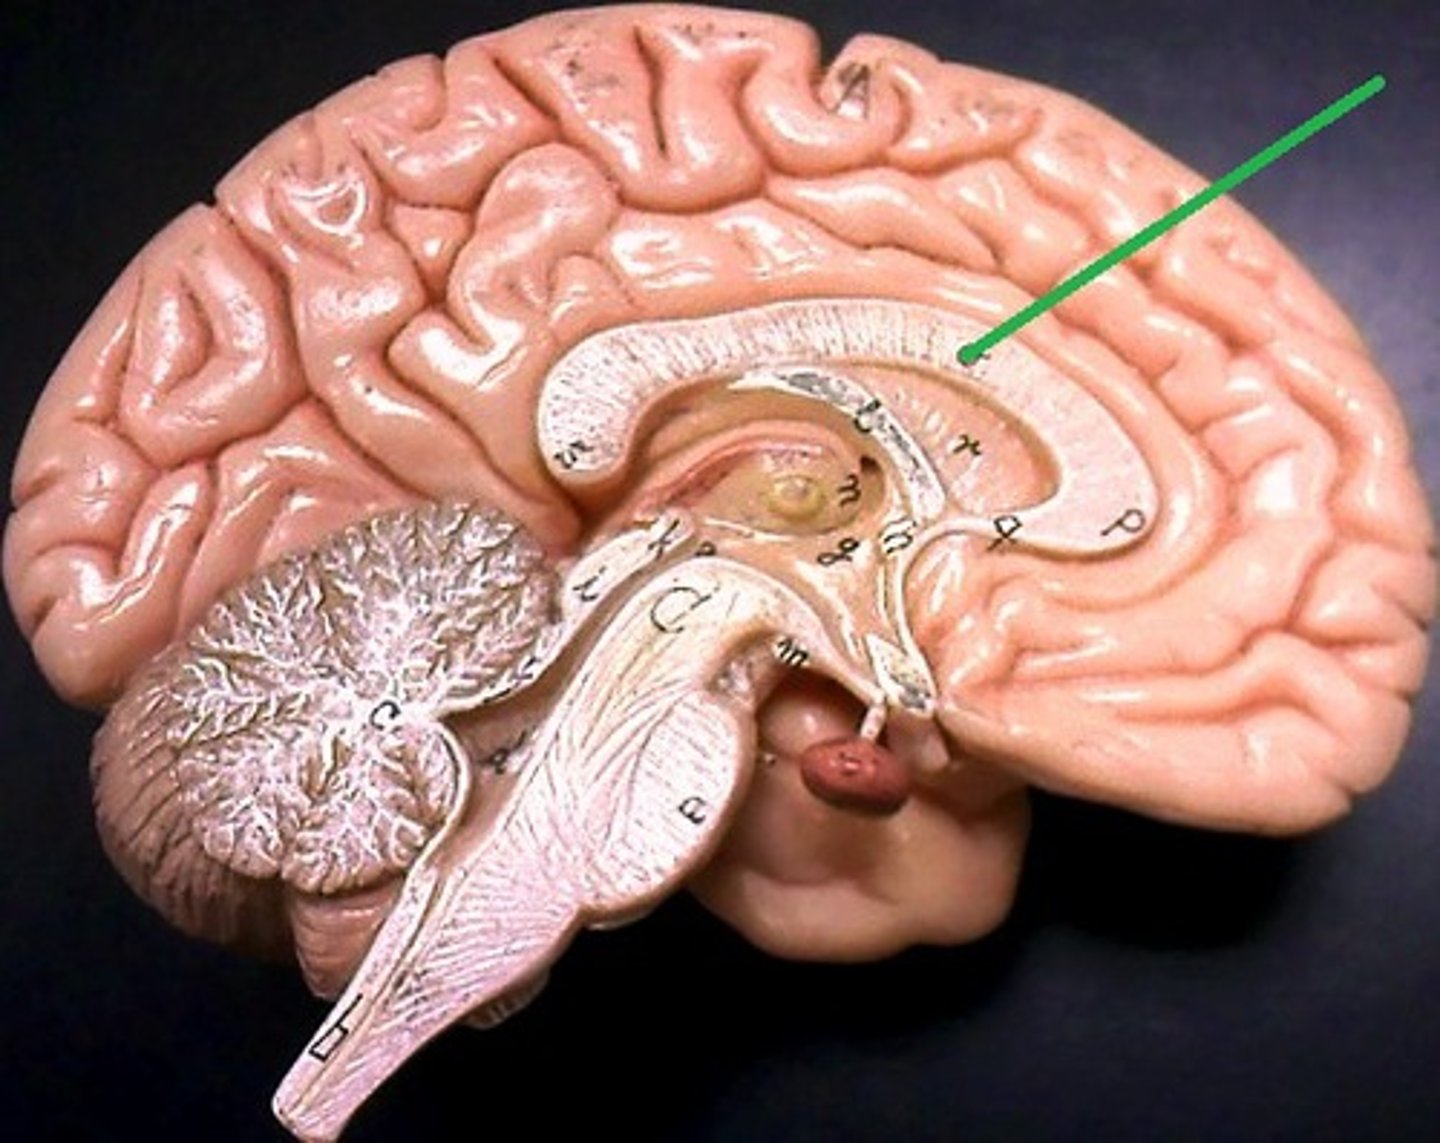

corpus callosum

fornix

diencephalon

thalamus

hypothalamus

infundibulum

pituitary gland

mammillary bodies

cerebellum

cerebellar cortex

arbor vitae

right and left lateral ventricles

third ventricle

fourth ventricle

cerebral aqueduct (mesencephalic aqueduct)

interventricular foramen